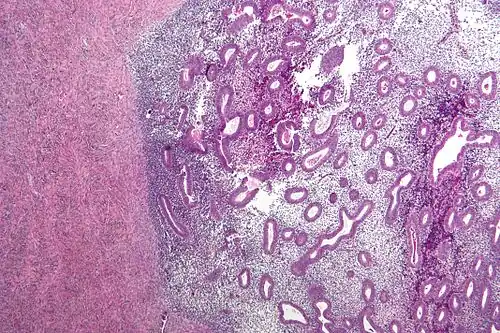

-

Endometriosis, abdominal wall -

Micrograph showing endometriosis (right) and ovarian stroma (left) -

Micrograph of the wall of an endometrioma. All features of endometriosis are present (endometrial glands, endometrial stroma and hemosiderin-laden macrophages).